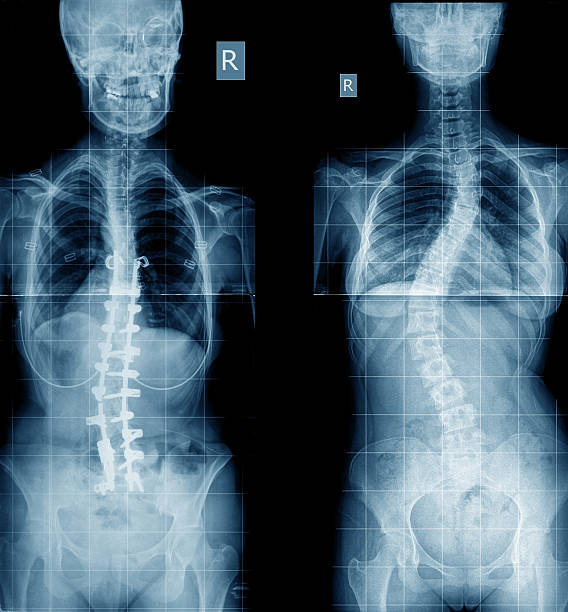

척추측만증은 척추의 공간 침범으로 인해 발생하는 질병으로, 이로 인해 척추의 굽힘이나 비틀림이 발생할 수 있습니다.